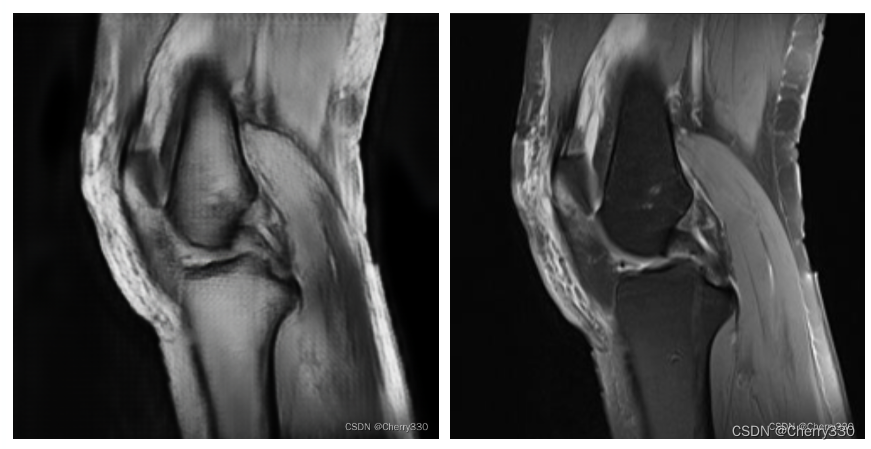

测试结果如图11。

图11 测试结果(左:生成图,右:原图)